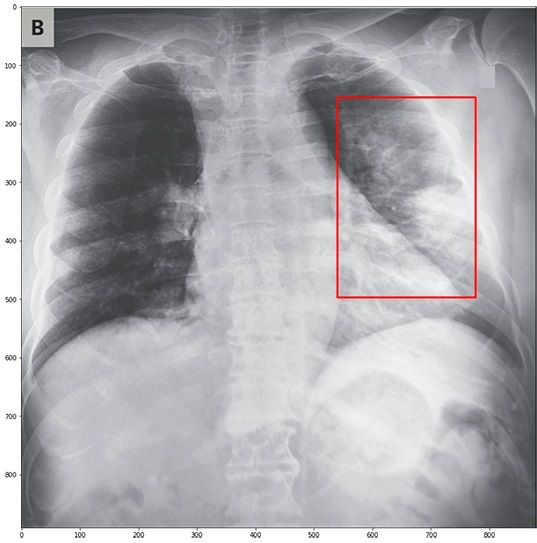

Ученые из университета Иннополис научили нейросеть диагностировать признаки COVID-19 на основании медицинский снимков с точностью 80%.

Разработчики Центра искусственного интеллекта российского ИТ-вуза обучали ИИ на 28 тысячах медицинских изображений лёгких здоровых людей и пациентов с разными видами пневмонии. Кроме того, на момент начального обучения у них в базе было 94 изображения, полученных у больных коронавирусом. Следующим этапом разработки должен стать запуск онлайн-сервиса, помогающего врачам при массовой диагностике во всём мире в режиме реального времени выявлять больных с развившейся коронавирусной пневмонией.

COVID-19 широко распространился по всему миру с тех пор, как первый случай был обнаружен в конце 2019 года. Ранняя диагностика заболевания важна для лечения и изоляции пациентов для предотвращения распространения вируса. Специалистами ИТ-вуза довольно оперативно до начала массовой самоизоляции в России была адаптирована модель под решение новых задач. Включив в набор данных алгоритма рентгеновские изображения органов грудной полости инфицированных COVID-19, взятые из открытого датасета на сайте Github и ежедневно пополняемого, ученые научили нейронную сеть выявлять общие признаки патологий, вызванных смертельным заболеванием.

Алгоритмом и врачем-рентгенологом были независимо проанализированы снимки зараженных опасным вирусом. Предсказания модели о наличии или отсутствии патологии совпадают с описаниями врачей в восьмидесяти процентах случаев. Кроме этого, алгоритм не ошибся в тринадцати процентах из ста в ситуациях, когда врач не сумел определить патологию. Ученые полагают, что как только размеры датасетов рентгеновских изображений с коронавирусом существенно пополнятся, точность алгоритмов возрастет.